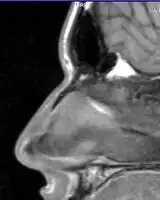

Nasal fractures are usually identified visually and through physical examination.[1] Medical imaging is generally not recommended.[1][2] A priority is to distinguish simple fractures limited to the nasal bones (Type 1) from fractures that also involve other facial bones and/or the nasal septum (Types 2 and 3). In simple Type 1 fractures X-Rays supply surprisingly little information beyond clinical examination. However, diagnosis may be confirmed with X-rays or CT scans, and these are required if other facial injuries are suspected.[2]

Nasal bone fracture

Bilateral nasal fracture as seen on CT scan